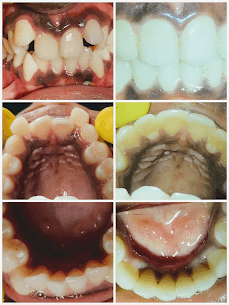

Twin Block Treatment

4-year treatment for 8-year-old with underdeveloped lower jaw using modified twin block